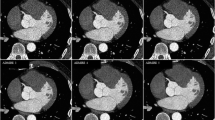

Figure 3 and 4 illustrate representative images for FBP, FBP50 %, and AIDR50 % reconstructions from the same subject. Image noise increased when reconstructing with FBP after a simulated 50 % dose reduction. The AIDR3D reconstruction 50 % dose reduction achieved smoothness of the structural border.

Representative axial (a–c) and corresponding curved multiplanar reformatted images (d–f) of the left anterior descending artery from three reconstruction methods performed on one subject (window width/level = 1,200/200). a and d were reconstructed using conventional filtered back projection (FBP); image noise increases in b and e that were reconstructed with FBP after a simulated 50 % dose reduction (FBP50 %). c and f were reconstructed with AIDR3D applied to the raw data after the application of the 50 % simulated noise reduction (AIDR50 %)